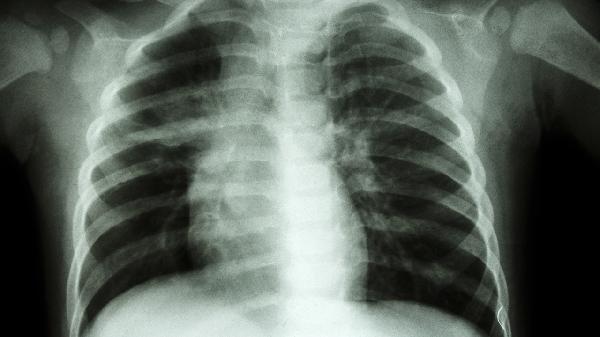

肺炎、胸膜炎、气胸等呼吸系统疾病常引发胸痛与呼吸困难。肺炎多伴有发热、咳嗽、咳痰,听诊可闻及湿啰音,胸部CT可见肺实变影。自发性气胸多见于瘦高体型青年,突发尖锐胸痛伴呼吸受限,X线显示肺组织压缩。慢性阻塞性肺疾病急性加重期也会出现胸闷气短,肺功能检查有助于诊断。